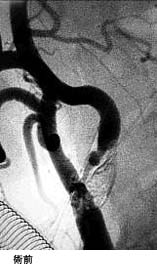

(1)破裂脳動脈瘤に対するGDC(コイル)塞栓術

*術後 コイルにより動脈瘤が写らなくなりました。